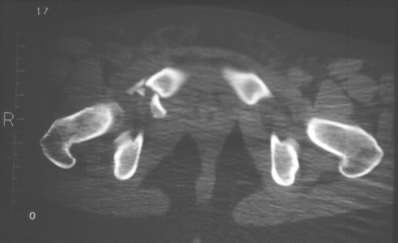

Radiographs:

Radiographs revealed a vertical buckle fracture of the right inferior sacrum, oblique fractures of the superior and inferior rami on the right and a fracture through the medial acetabulum. Obturator and iliac oblique inlet and outlet pelvic views, and a thin cut CT with 3-D reconstruction of the acetabulum were performed. These elucidated a comminuted anterior wall with fracture line extending to the posterior column. The posterior column was non-displaced. The pelvic fracture was non-displaced.

Assessment:

1. Right T-shaped acetabular fracture with anterior wall comminution.

2. Right pelvic fracture, lateral compression, displaced ;5 mm.